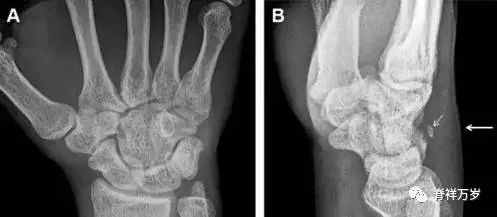

35.三角骨骨折

三角骨骨折是除舟状骨骨折外腕关节常见的骨折之一。其背侧是背侧桡腕韧带的附着点,因此背侧骨折更常见。常规正侧位片基本可明确诊断。背侧骨折可在侧位片上看到一小骨块。

图 6 三角骨骨折。(A)前后位片骨折不明显,(B)仅在侧位片上见一小骨块(短箭头),伴有软组织肿胀(长箭头)。

36.腕关节不稳定与脆弱区

月骨周围脱位和月骨周围骨折脱位常发生于摔倒后手掌撑地,由过伸、轴向*力暴**所致。所谓的「脆弱区」包括桡骨茎突、大多角骨、舟状骨、头状骨近端、钩状骨近端、三角骨的月骨缘、尺骨茎突。

图 7 经舟状骨骨折月骨周围脱位(腕关节前后位、斜位、侧位)。(A,B)前后位、斜位示月骨腰部骨折(黑箭头),第 1、2 腕弧中断,舟状骨近极(*)仍在原位,而远极(虚线)背侧脱位。